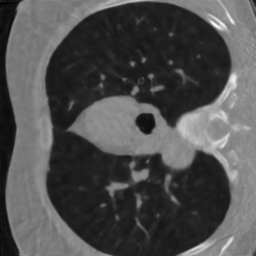

In our experiments, we consider a subsampling ratio of and , meaning that or respectively. The parameter encodes all the parameters above. The sensitivity maps and the trajectory perturbations are usually unknown, making MRI reconstruction a blind inverse problem. Examples of realistic sampling trajectories used in this work are displayed in Fig. 2, bottom.

Following [36], we generate random target densities as anisotropic power decaying distributions. They are parameterized by a random vector that encodes the density at origin, the anisotropy and the power decay law. To avoid solving (13) at training time, we have pre-computed sampling patterns. The corresponding vectors have been generated by using a max-min sampling (see [72, 25]) of a set of an admissible set of parameters . We refer to [36] for more details. Examples of densities and sampling patterns without constraints are displayed in Fig. 2(a)-2(e). Notice that we did not include trajectory constraints for generating this figure. They are taken into account for the blind inverse problem part.

For MRI reconstruction, we considered measurements coming from a single reception coil, to reduce the computational complexity. We used both the denoising network and the unrolled proximal gradient descent on different schemes: a radial one (, Fig. 2(a)), a horizontal one (, Fig. 2(b)) and a vertical one (, Fig. 2(c)). In addition, we used two crosses, which do not belong to the training family . The first one is aligned with the axes (, Fig. 2(f)) and the other one with the diagonals (, Fig. 2(g)).